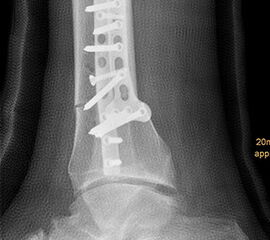

Wir benutzen zur Osteosynthese 3,5 mm LCP T-Platten. In der intraoperativen Röntgenkontrolle kann im seitlichen Bild die Zentrierung des Talus überprüft werden, und ggf. durch eine milde extendierende oder flektierende Korrekturkomponente verbessert werden 18. Eine begleitende Deformität der Fibula korrigieren wir üblicherweise mit einer z-förmigen Osteotomie die wir mit einem 1/3 Rohrplättchen sowie einer Zugschraube sichern 18.